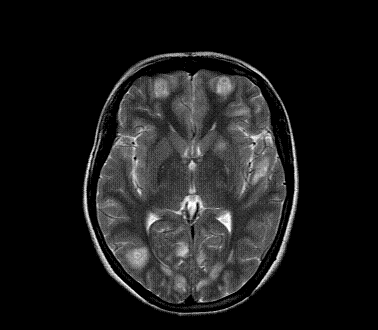

以下是引用xly在2009-5-20 11:38:00的发言:[br]大脑、小脑及脑干多发结节状及环状稍长t1、长t2异常信号影,部份病灶中心见稍短t1、短t2信号,病灶边缘光滑、边界清楚,灶周环状水肿,dwi为低信号,增强扫描上述病灶均匀强化,部份病灶中心无强化,脑膜小结节异常强化,考虑脑膜脑结核可能性大。胸片如何?ppd如何?期待结果。